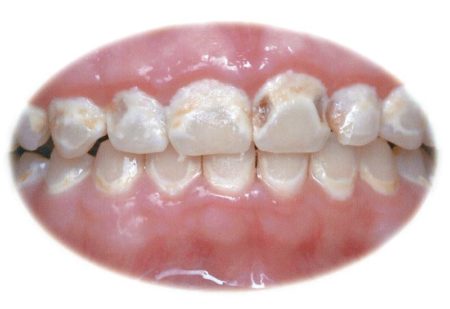

Voir la description détailléeSolution simple et intelligente pour les orthodontistes, Ortho-Coat permet de créer une couche protectrice autour des brackets pour réduire ou éliminer le développement des lésions carieuses, des décalcifications et des décolorations. Les brackets peuvent être de véritables pièges à nourriture, et sont à même de former une plaque que les patients ne peuvent pas nettoyer. Les résultats peuvent être désastreux.